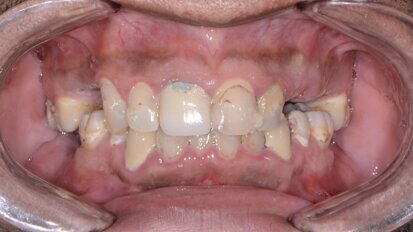

Motivated by his desire to simplify the treatment process for patients, Dr Philip Tan has developed a full-arch implant-retained prosthesis for completely ...